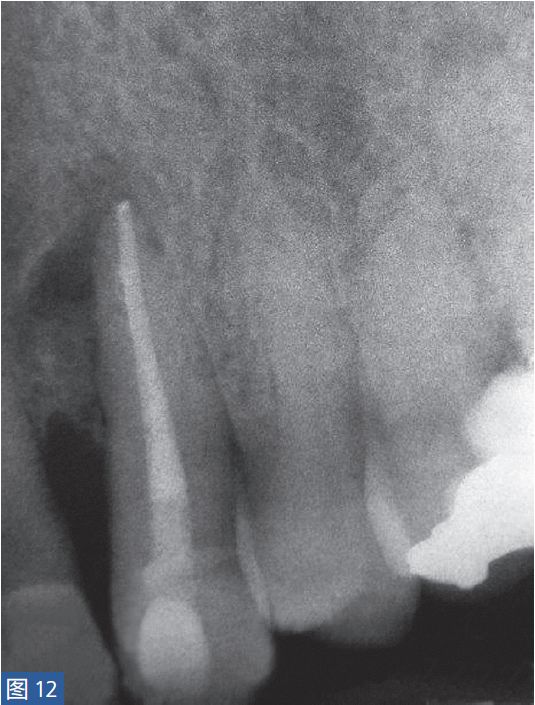

根尖周囊肿伴无症状性根尖周炎(AAP)根尖周囊肿(图12 和13)总是与无症状的根尖周炎相关。目前普遍认为,通过上皮残留细胞的炎性增殖形成了根尖周囊肿。在组织学上,它们分为袋囊肿和根尖周真性囊肿。通常认为,袋囊肿可以通过单纯的根管治疗而非手术方式,即通过细胞凋亡和程序性细胞死亡达到愈合。这种方式在真性囊肿似乎不太可能实现。

图12:23 牙齿根尖周囊肿 。非手术治疗,采取单纯的根管治疗后的X 线片检查。因未愈合而决定采取手术治疗。

图13:手术性根管治疗一年后的对照X 线片显示根尖病灶已愈合。对搔刮出的组织进行组织病理学检查显示为真性根尖周囊肿。